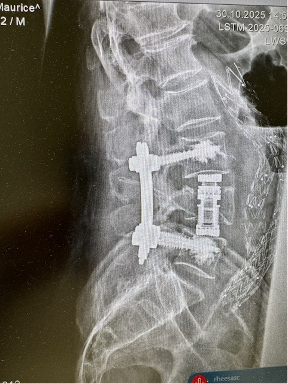

In more complex fractures, stabilization of the spine using screws and rods may be required.

These procedures help restore spinal alignment and provide long-term stability.

Whenever possible, these procedures are performed using minimally invasive techniques, which allow smaller incisions, less tissue disruption, and faster recovery.

Patient fell from ladder and developed lumbar L4 fracture, he was addressed in minimal invasive technique with L4 replacement and stabilisation. He was able to ambulate without any aids on day 1 after surgery